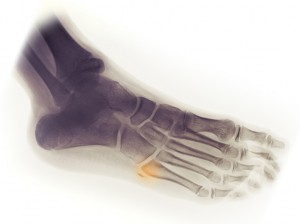

Fractura del quinto metatarsiano. Es una lesión que ultimamente se esta dando mucho en el mundo del fútbol. Se piensa que puede estar provocada por una sobrecarga de entrenamiento en la zona afectada lo que hace que los tendones peroneos se recarguen produciendo así la lesión. Muchas de las veces que ocurre el jugador ni siquiera lo percibe y se da cuenta después del partido.